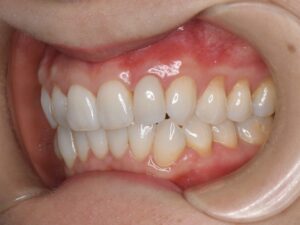

ジルコニアオールセラミッククラウンによる再補綴を行った。当然ながら、歯肉圧排(2重圧排)とシリコン印象による精密印象を行っている。

歯の色合い、歯茎の反応も良く、自然な感じで仕上がっている。